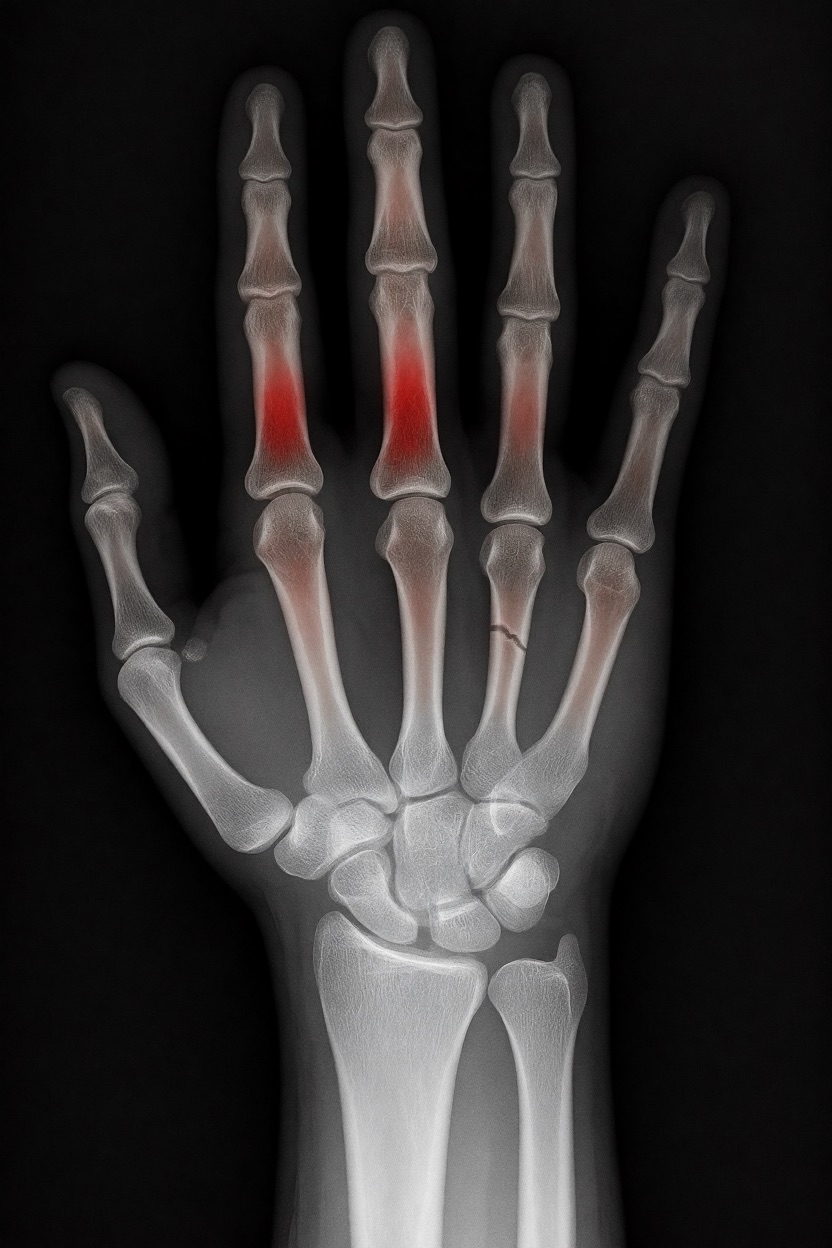

テスト結果:

- 偽陽性 ≈ 24%

- 骨折検出 ≈ 20%

感度モード(検出を優先、ノイズ多め)

- Euler、15ステップ、Karras

- Denoise:1.0

結果:

- 偽陽性 ≈ 80%

- 骨折検出 ≈ 86%

さらに攻撃的な設定(例:rk beta57、Denoise 1.0)では、**偽陽性100%、検出100%**という馬鹿げた結果に:すべてを赤で塗りつぶし、健常部もほぼすべて骨折と誤認する。未経験の目には区別がつかない。